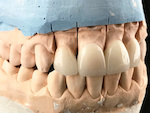

虫歯治療で使われる素材として、白い詰め物と銀歯が一般的です。白い詰め物は、自然な歯の色に近く、美しい仕上がりが特徴です。一方、銀歯は金属で作られており、強度が高いため、奥歯などに使われることが多いです。

どちらを選ぶかは、患者の希望や歯の位置、治療の重要性などに基づいて決まります。